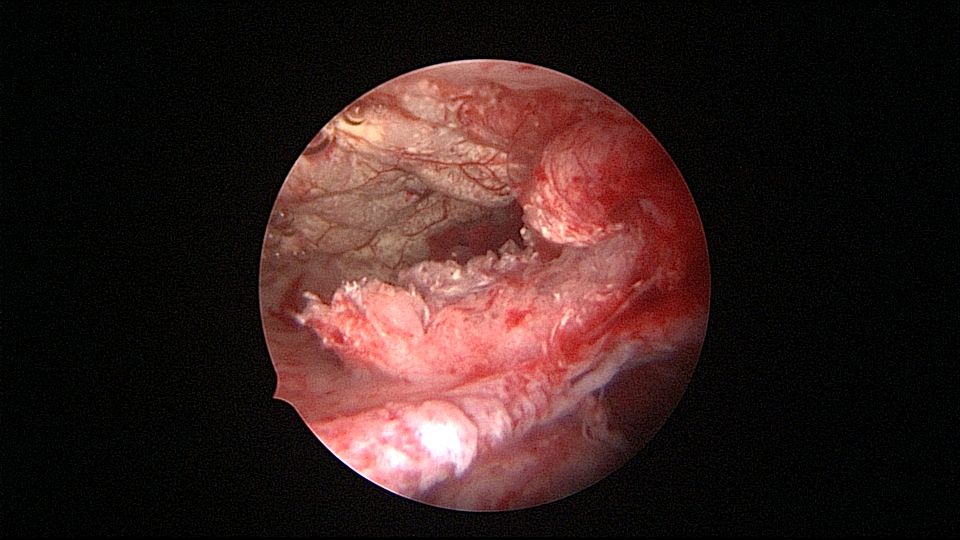

患者55岁,G4P1,顺产1次。安环16年,绝经5年,外院取环失败。子宫前位,宫颈萎缩,宫腔下段左后壁见假道,假道内见肌瘤结节突出,爱母环位置正常,宫腔左侧壁及前壁见占位质脆组织,表面有异常粗大血管。异物钳顺利取出节育环,占位组织病检为内膜样癌。取环造成的假道让病人因祸得福,提前发现了子宫内膜样癌,得以及时手术治疗。